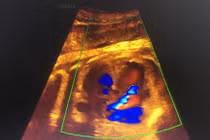

(khoahocdoisong.vn) - Khi mắc hội chứng truyền máu song thai nếu không được điều trị thì 90 - 100% thai sẽ chết. Còn nếu một trong hai thai chết thì 25% thai còn lại bị di chứng thần kinh nặng nề. Bệnh viện Phụ sản Hà Nội là bệnh viện đầu tiên trong cả nước thực hiện được kỹ thuật.

(khoahocdoisong.vn) - Siêu âm còn là phương pháp bắt buộc trong theo dõi sản khoa, giúp bà mẹ thêm an tâm về sự phát triển toàn diện của con trước khi chào đời.